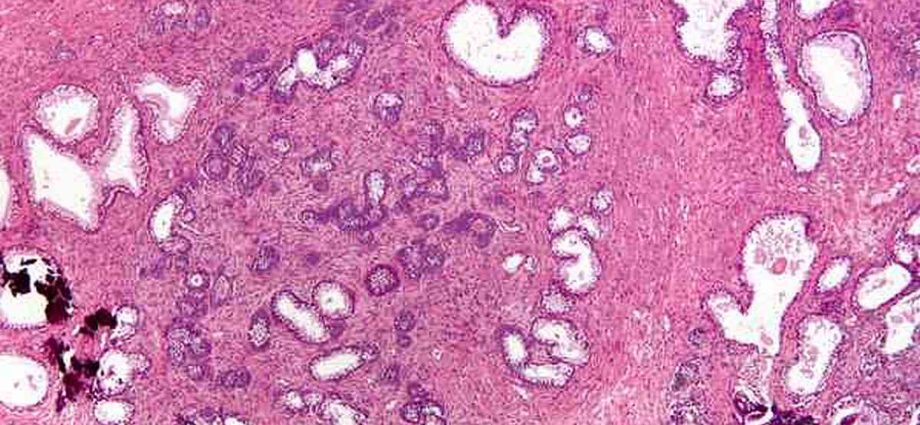

Pratiquement tous les organes, tous les tissus et toutes les cellules sont soumis à ce renouvellement cellulaire permanent et vont être complètement régénérés plusieurs fois dans une vie, à une fréquence plus ou moins élevée en fonction des cellules. Ce qui fait qu’au bout du compte, l’immense majorité des cellules et des organes sont plus jeunes que l’individu lui-même.

Ce vaste écosystème cellulaire – qui est finalement notre organisme – contient environ 250 types de cellules différentes. La grande majorité est soumise au renouvellement cellulaire, sauf quelques exceptions, comme, par exemple, les neurones et les cellules cardiaques où le renouvellement est très lent ou quasi inexistant.

Faisons un petit tour dans ce monde fascinant qui nous donne une meilleure compréhension des cellules, de notre corps, mais également des pathologies qui peuvent en résulter.